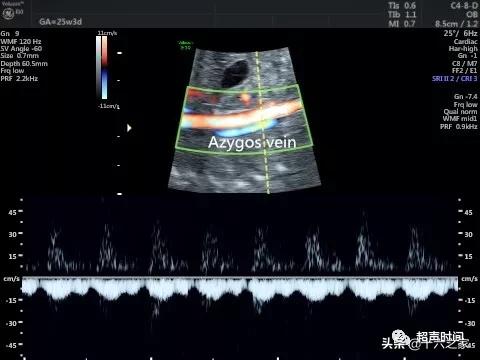

图 1 和视频 1 臀位胎儿腹部横切面示腹主动脉位于脊柱左前方 , 未见下腔静脉 , 扩张的奇静脉位于腹主动脉右后方 , 胃泡位于左侧腹腔 , 脐静脉弓背朝向胃 。 SP :脊柱;DAO :降主动脉;Azygos vein :奇静脉;ST :胃泡;UV :脐静脉

图 2 和视频 2 CDFI 示主动脉及扩张的奇静脉血流